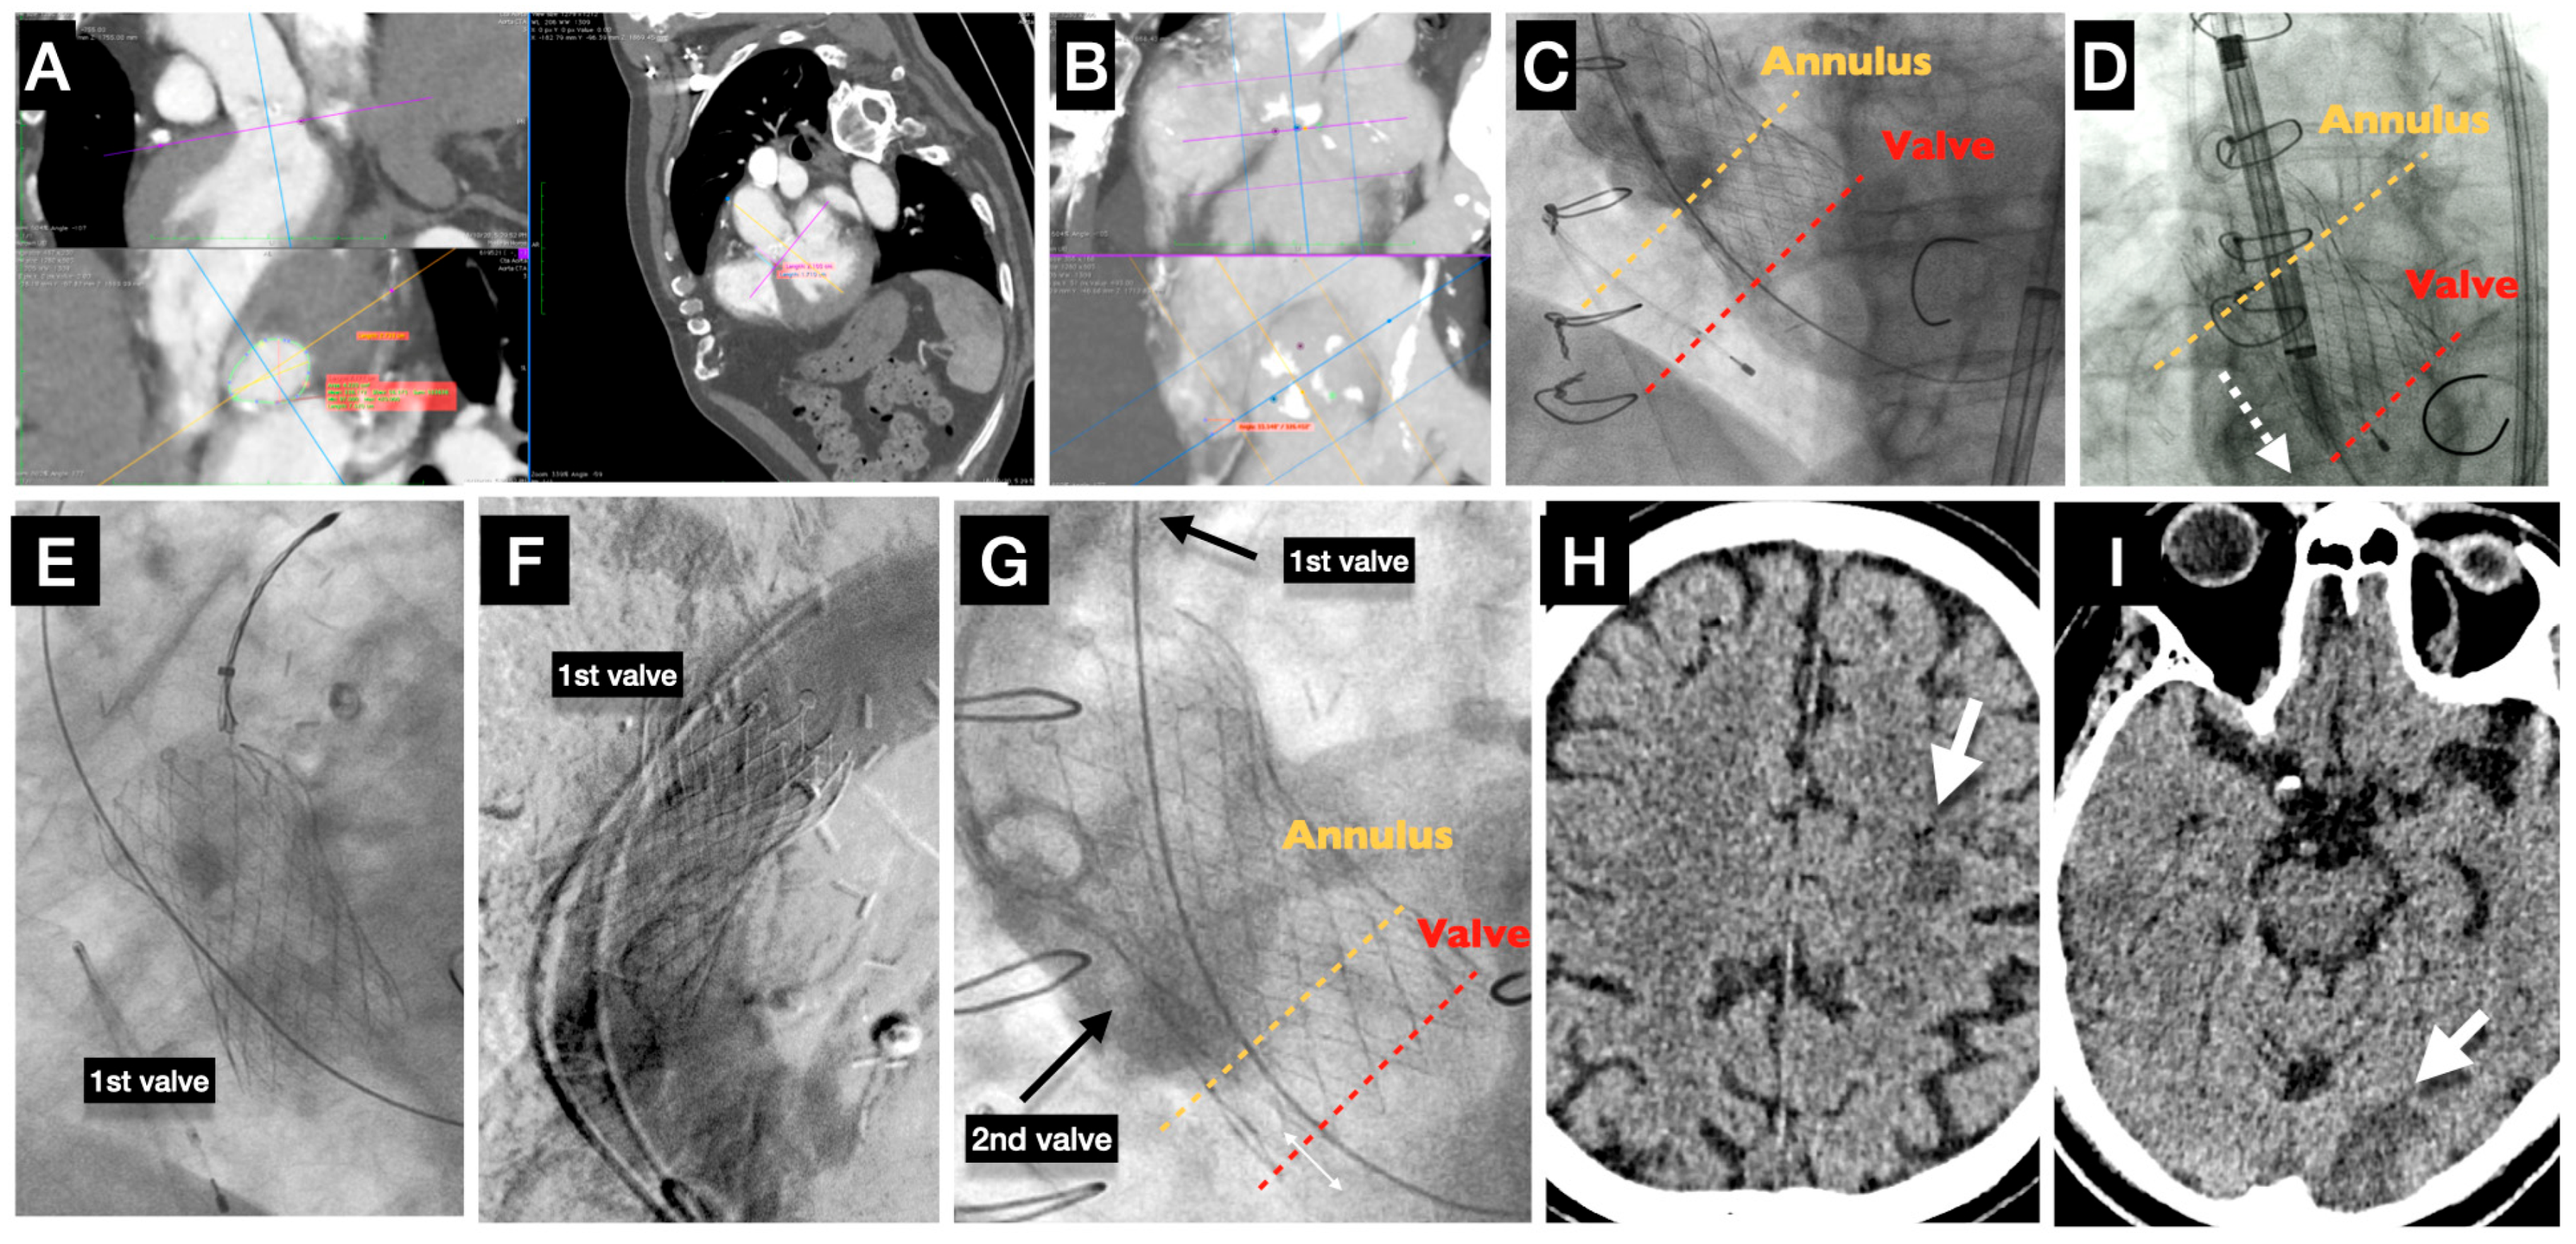

6. Pathophysiology and Technical Aspects Behind Stroke Causes (Figure 2)

7. Acute Stroke (Case Example)